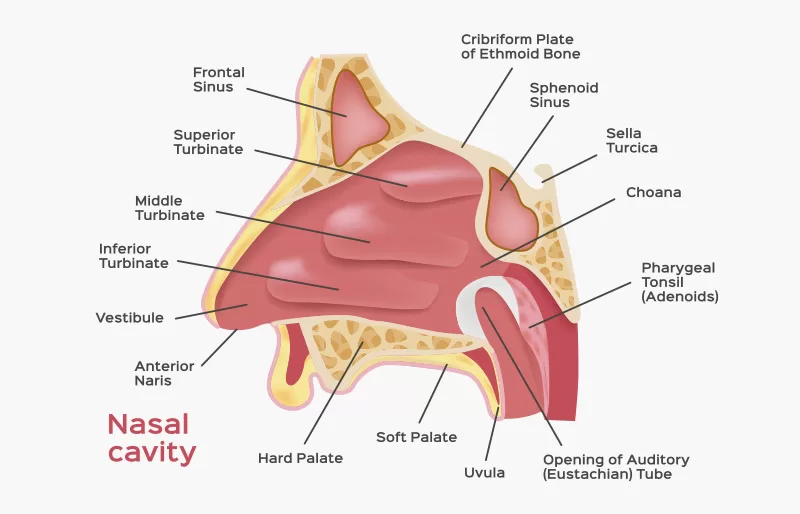

1. Hidung (Cavum Nasalis)

Rongga hidung berlapis selaput lendir berfungsi menangkap benda asing yang masuk lewat saluran pernapasan, di dalamnya terdapat beberapa struktur penyusun.

- Kelenjar minyak.

- Kelenjar keringat.

- Rambut pendek dan tebal yang berfungsi menyaring partikel kotoran yang masuk bersama udara.

- Konka yang mempunyai banyak kapiler darah yang berfungsi menghangatkan udara yang masuk.